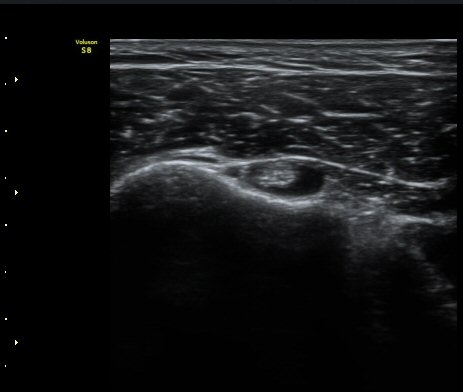

¾ÊÀ¸³ª(±×¸² 5) ±Ø»ó°Ç ¿ÜÃø¿¡¼­ ´ë°áÀý ÇÇÁú°ñ ¿¬°á¼º ¼Ò½ÇÀ» º¸ÀδÙ(±×¸² 6). ±ØÇ졂 Á¾´Ü¸é

°Ë»ç»ó(±×¸² 7) ƯÀÌ ¼Ò°ßÀ» º¸ÀÌÁö ¾Ê´Â´Ù. ±Ø»ó°Ç Ⱦ´Ü¸é °Ë»ç»ó ±Ø»ó°ÇÀÇ ±ÙÀ§ºÎ¿¡¼­´Â

ƯÀÌ ¼Ò°ßÀ» º¸ÀÌÁö ¾ÊÀ¸³ª(±×¸² 8) ±Ø»ó°Ç ¸»´ÜºÎÀ§¿¡¼­ ´ë°áÀýÀÇ °ñ °áÇ̰ú ÇÇÁú°ñ ¿¬°á¼º

¼Ò½ÇÀ» º¸ÀδÙ(±×¸² 9, 10).